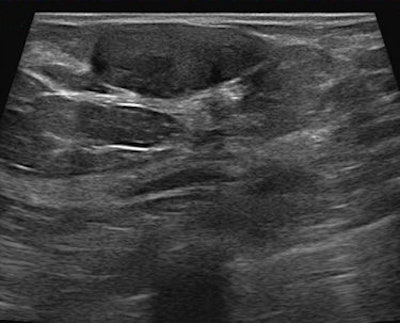

Ultrasound confirms the lesion as a solid homogeneous mass, parallel to the skin. These features suggest a fibroadenoma, but this lesion meets the criteria of the BI-RADS 3 category. Follow-up showed no changes over two years.Each PROCAS participant fills out a two-page questionnaire that includes questions about lifestyle, family history, weight, height, ethnicity, reproductive history, and other questions related to risk factors, with genetic material being taken from about one-sixth of the women. All participants are undergoing routine screening, of course, so their mammograms will be analyzed and incorporated with other findings. Finally, women who are determined to be at high risk -- along with some low-risk participants -- are offered a consultation to receive advice, and, when appropriate, therapeutic intervention, Astley said.